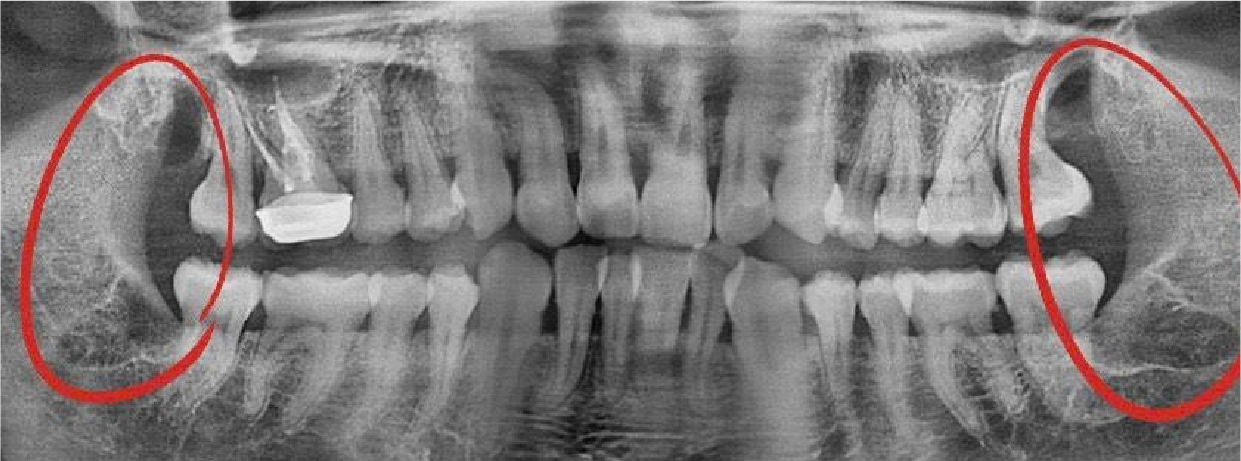

Bác sĩ kiểm tra tổng quát khoang miệng, chụp phim X-quang hoặc CT 3D để xác định vị trí, mức độ tổn thương và lập kế hoạch điều trị.

Hình Ảnh Trước & Sau Điều Trị

Minh chứng rõ ràng cho chất lượng và hiệu quả tại Nha khoa Như Ngọc – nơi mỗi khách hàng đều tìm lại được nụ cười tự tin sau quá trình điều trị và thẩm mỹ răng